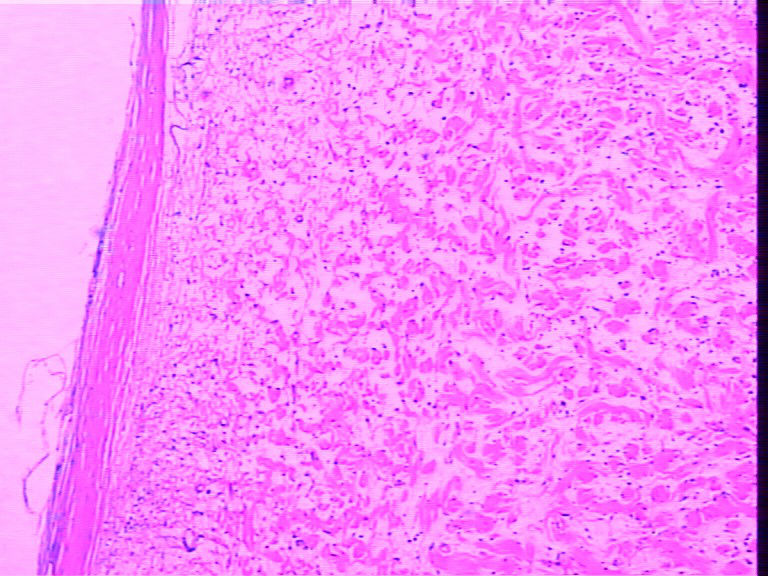

腹壁一个包块,大小4cmx2cmx2cm,椭圆形,有菲薄包膜,淡黄色,切面淡黄色半透明,质地偏韧。

是女性患者,19岁。考虑为神经方面肿瘤,等着病人过来加做免疫组化。